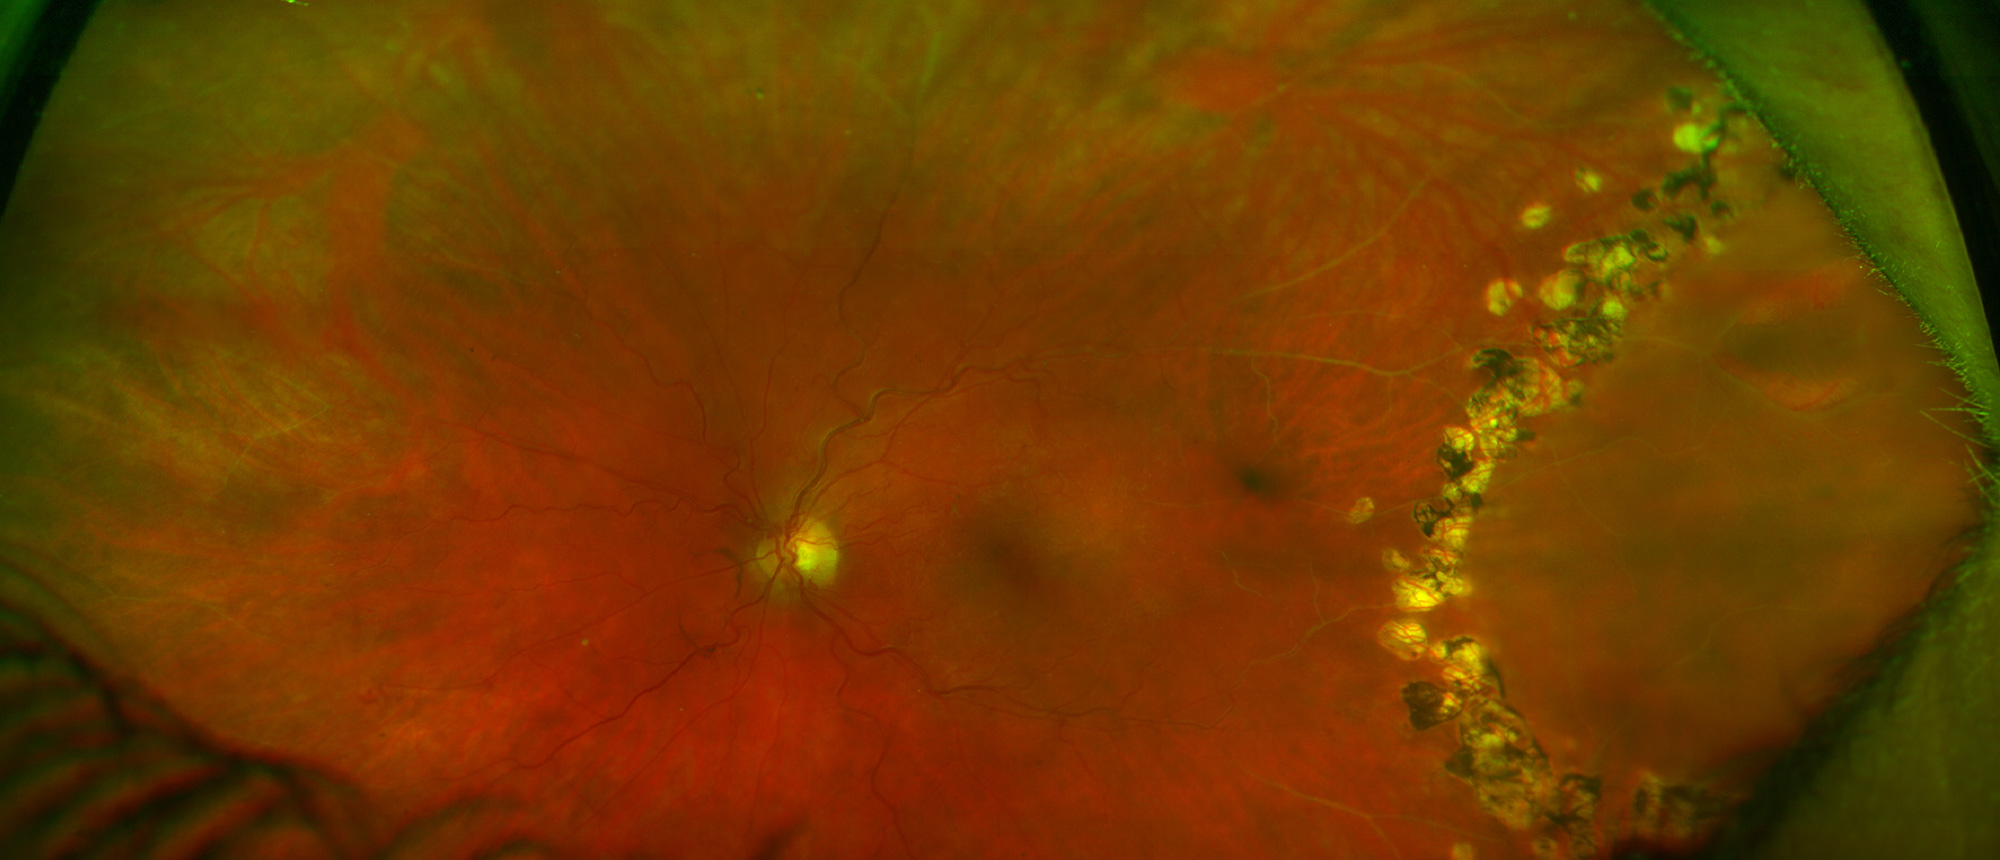

Pseudoangiomatous Retinal Gliosis

Specialty: Retina and Vitreous Diseases

Type: Ophthalmic Images

Include in Catalogue?: Yes

Original Contributor(s): Luis J. Haddock, MD; Marilyn A. Marquez, MD

Presenter/Faculty: Haddock, Marquez

Figure 1: Fundus photography of patient treated with Iodine plaque, PPV and endolaser due to Pseudoangiomatous retinal glisois that caused a retinal detachment. Figure 2: Bscan of same patient as figure 1 before surgery.